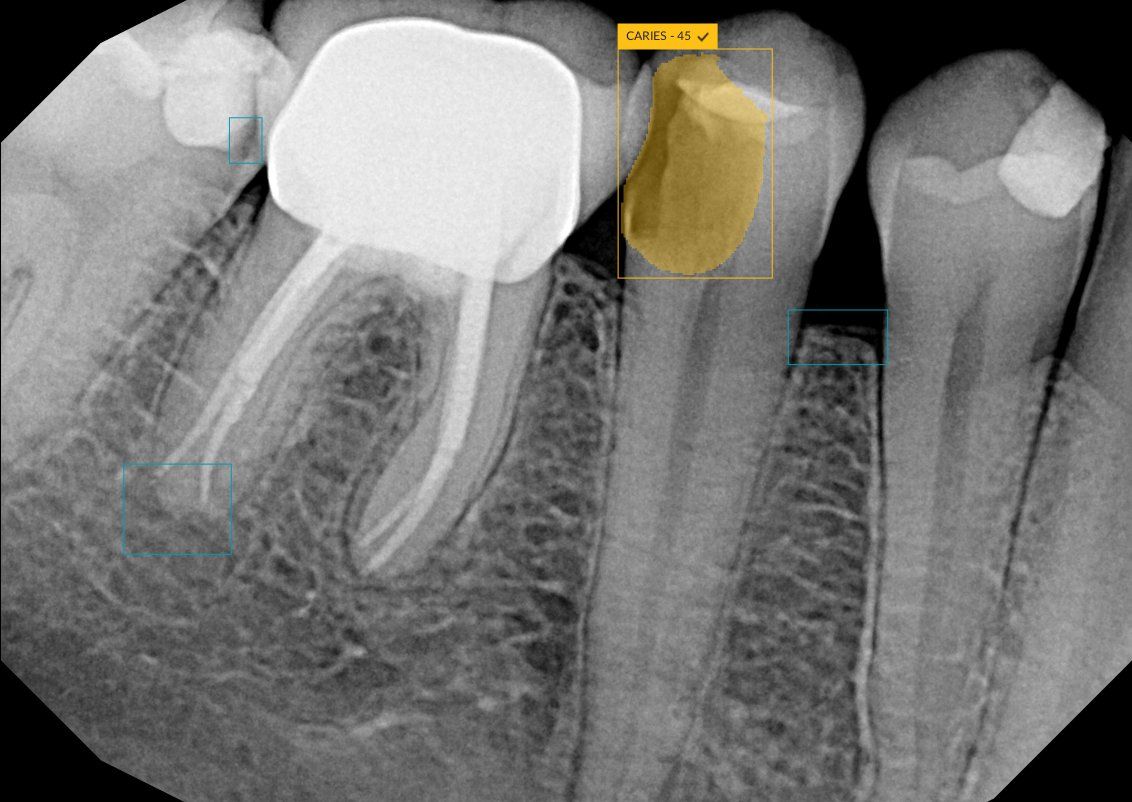

The CS 9600 features breakthrough innovations such as its artificial intelligence (AI)-powered positioning, video cameras, and Live Positioning Assistant to help enable users to produce high-quality images.